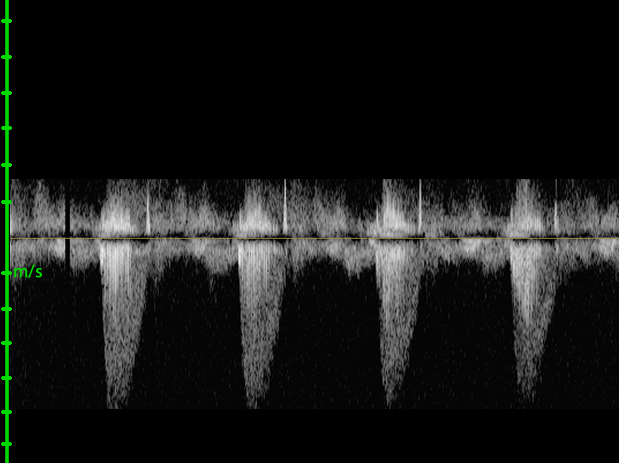

Zoom Gain Contrast Sepia